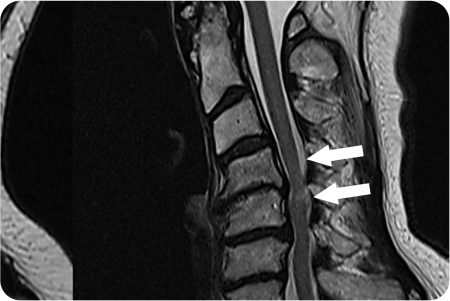

3

관절경하

척추체 성형술

피부에 작은 절개를 내고, 가느다란 바늘을 통해

골절된 척추 뼈 내부에 접근합니다. 골절된 척추 뼈

내부에 특수 의료용 시멘트(골시멘트)를 주입하여,

뼈를 단단히 고정하고 통증을 줄입니다.